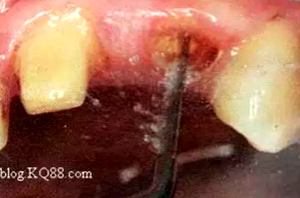

根管壁殘留物的存在直接影響纖維樁的粘接和固位,這也是導(dǎo)致纖維樁脫落的主要原因。

(根管內(nèi)殘留物)

個(gè)人見解:必要的情況下先開闊根管口建立一定的視角后,慢速手機(jī)上G鉆為引導(dǎo)鉆,由號(hào)遞增引導(dǎo)開闊通路;P鉆預(yù)備樁道,同樣需要由小向大號(hào)遞增,直到選擇好適合的號(hào)預(yù)備到規(guī)定測(cè)量的深度即可,再配合纖維樁系統(tǒng)中各型號(hào)纖維樁所匹配的樁道鉆,預(yù)備、修整成與纖維樁相適應(yīng)的樁道。

預(yù)備后根管壁上會(huì)不同程度的牙膠和封閉劑等殘留物,所以樁道預(yù)備前后建議X線片輔助檢查預(yù)備深度等情況,而殘留物也會(huì)很清晰地顯現(xiàn)。